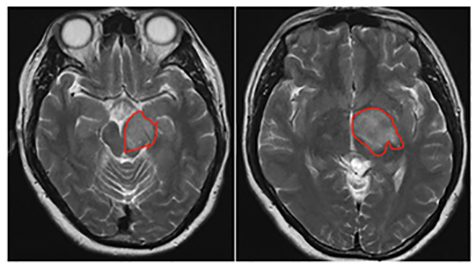

2、30多岁王女士,左侧基底节区、脑干左侧缘异常信号,对比三个月前的片子片少许增大,考虑低级别胶质瘤可能性大。